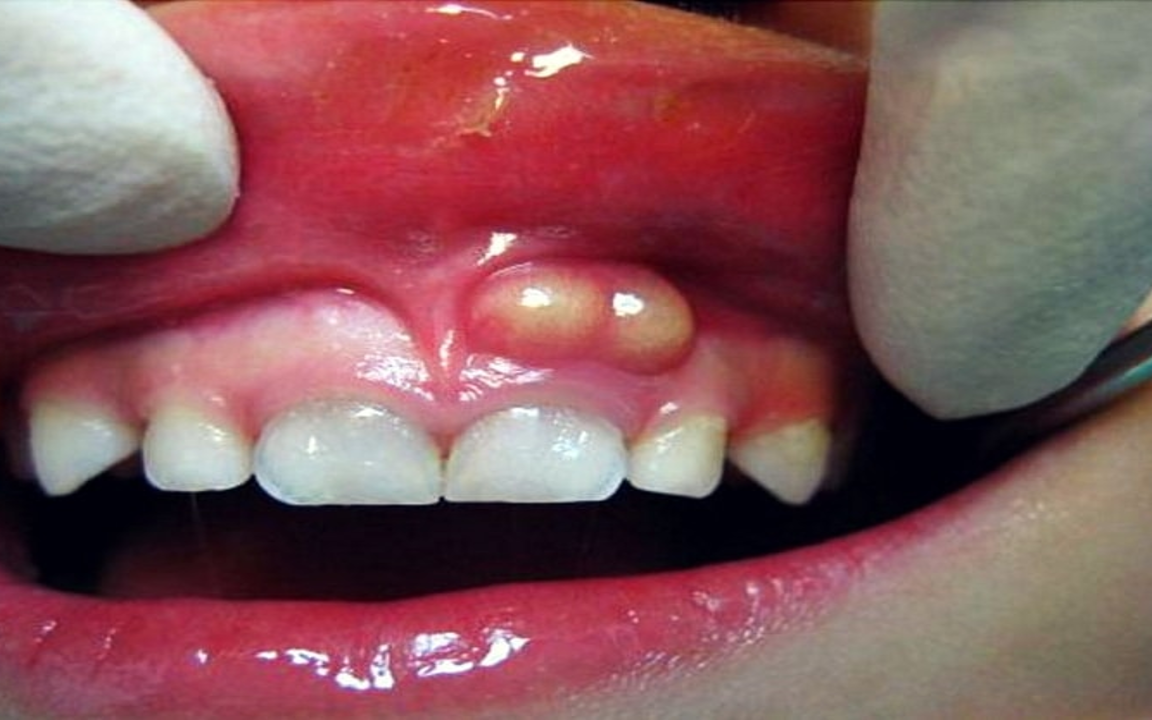

شكل خراج الأسنان في الأشعة

وفيما يخص شكل خراج الأسنان في الأشعة، فإنه يكون هناك بؤرة غامقة في الضرس تظهر في الأشعة السينية التي يجريها الطبيب قبل التدخل بوصف الدواء أو الجراحة، كما يحدد الطبيب من خلال الأشعة مدى انتشار الخراج في الأسنان المجاورة، وهناك مؤشرات تكشف أن المريض يعاني من خراج تكون كالآتي:

- يكون هناك تورم في الوجه في أحد الجانبين

- عدم القدرة على المضغ أو تناول الطعام

- صداع شديد في الرأس يمتد إلى الأذن

- كما يكون هناك ألم شديد غير محتمل.